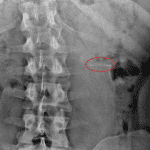

- Bubbly lytic lesion in the left ischium and inferior pubic ramus

Bubbly lytic lesion in the left ischium and inferior pubic ramus without aggressive features, likely a benign lesion such as an aneurysmal bone cyst. Correlation with prior imaging, if available, would be useful to document stability. Otherwise, consider CT or MRI for further evaluation.